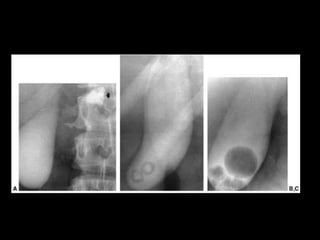

Técnicas de Imagem •Rx: – 10 – 15% das colelitiases, estão calcificadas e identificáveis no RX – Pode ser visto também a vesícula em “porcelana.” – Gás pode ser visto dentro das pedra: Sinal de Mercedes-Benz – Colecistografia oral: Ingesta de composto iodado. Atualmente susbstituído pelo US